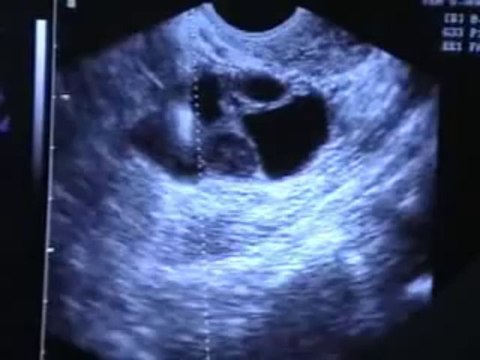

In Vitro Fertilization (IVF) is undoubtedly a blessing for couples facing difficulty in conceiving naturally. In IVF, the egg fertilization happens in lab and embryo is inserted in the uterus. Jiyo India can help in getting successful yet affordable IVF treatment in India with ease. Contact Jiyo India Pvt. Ltd at [email protected] and call +91 8810611368, +91 8810601324 and get the Medical Services Simplified at Low Cost with Fast Procedure Visit us: bit.ly/2eK5IHb